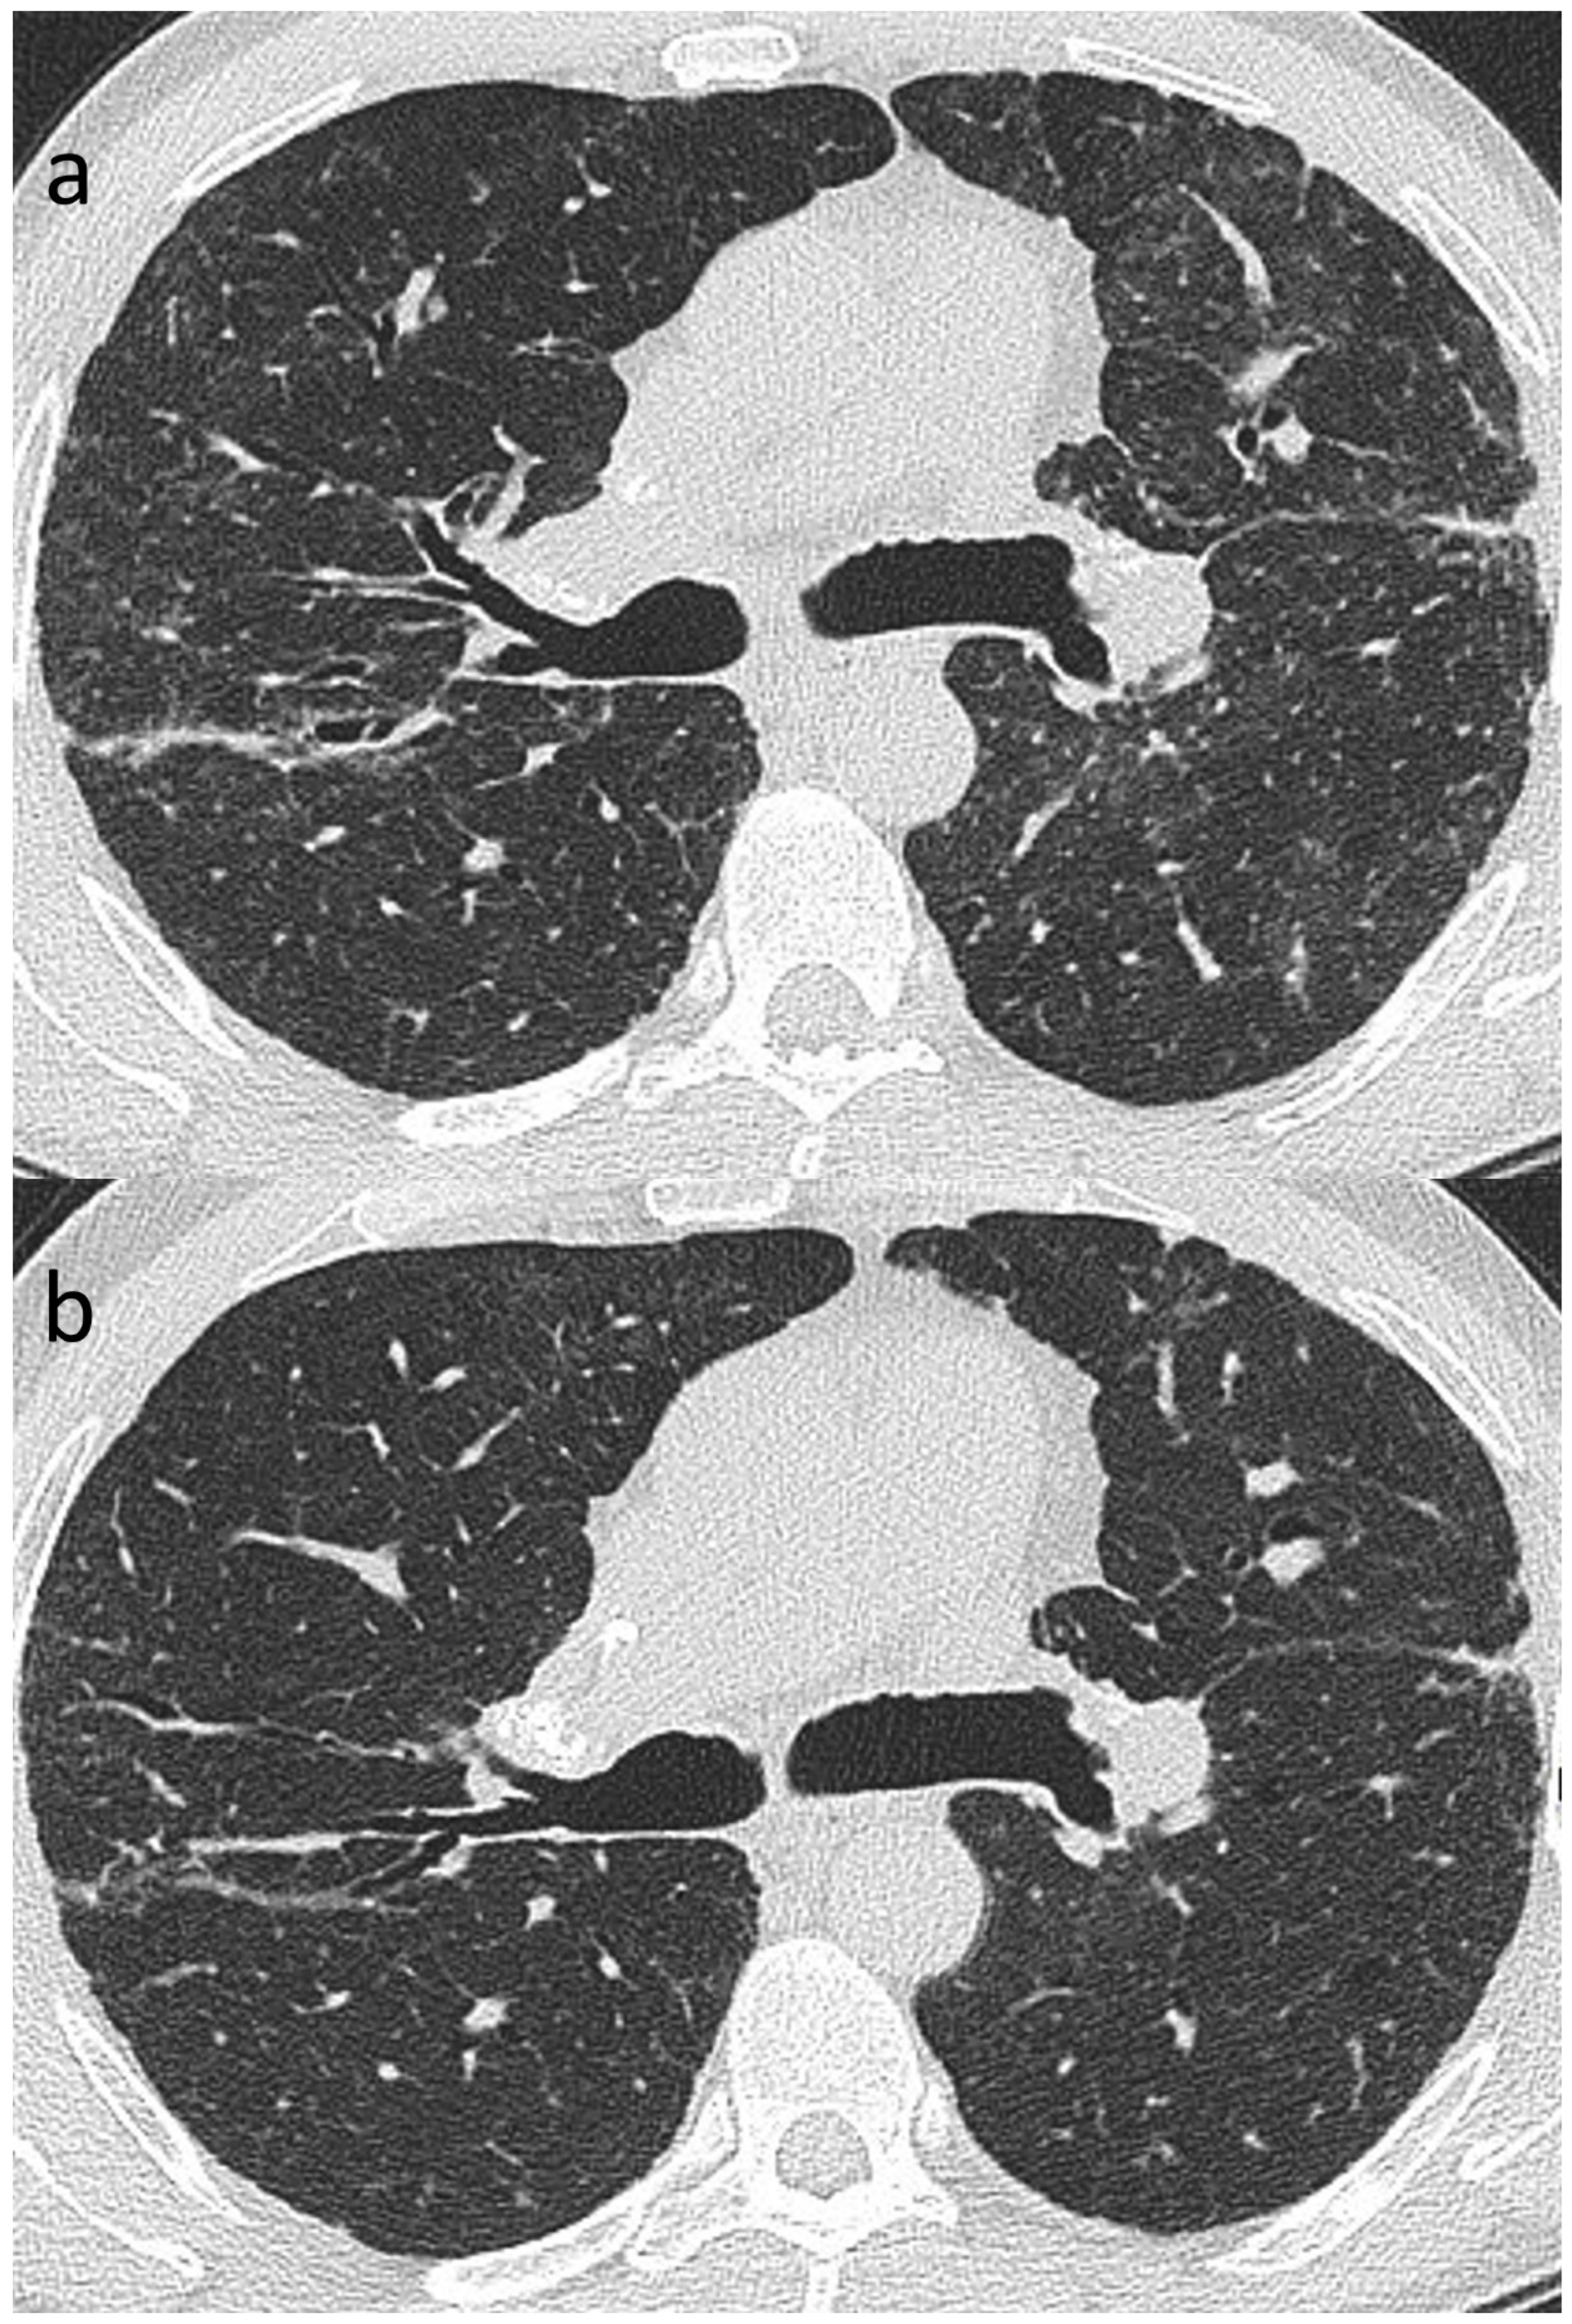

Of the variety of CT patterns reported in sarcoidosis, nodular infiltrates are most likely to improve or resolve at follow-up [41]. Additionally, peribronchovascular thickening, consolidation and ground-glass opacification also have the potential to resolve completely [41,49,130], particularly with treatment [49] (Figure 8a,b). While linear opacities may clear, Murdoch and co-workers found an increased likelihood of progression over time and more so than with other morphologic features [41]. The natural history of ground-glass opacities is more difficult to predict and this CT pattern is a poor predictor of both disease activity and prognosis [41,49]. In part, this might be due to the non-specificity of CT ground-glass opacification which might indicate ‘active’ (and therefore potentially reversible) granulomatous inflammation or irreversible fine fibrosis below the limits of CT resolution [50]. CT abnormalities tending to indicate irreversible disease include reticulation, architectural distortion, honeycombing and traction bronchiectasis/bronchiolectasis. However, while some patients inevitably progress despite treatment, relative stability over time is more common in sarcoidosis-related ILD than in overtly progressive fibrotic DILDs [108].

Figure 8.

(a,b): Reversible disease in sarcoidosis. Targeted images of the left mid-zone showing the resolution of multiple random micronodules over time in (a) 2015 and (b) 2017.